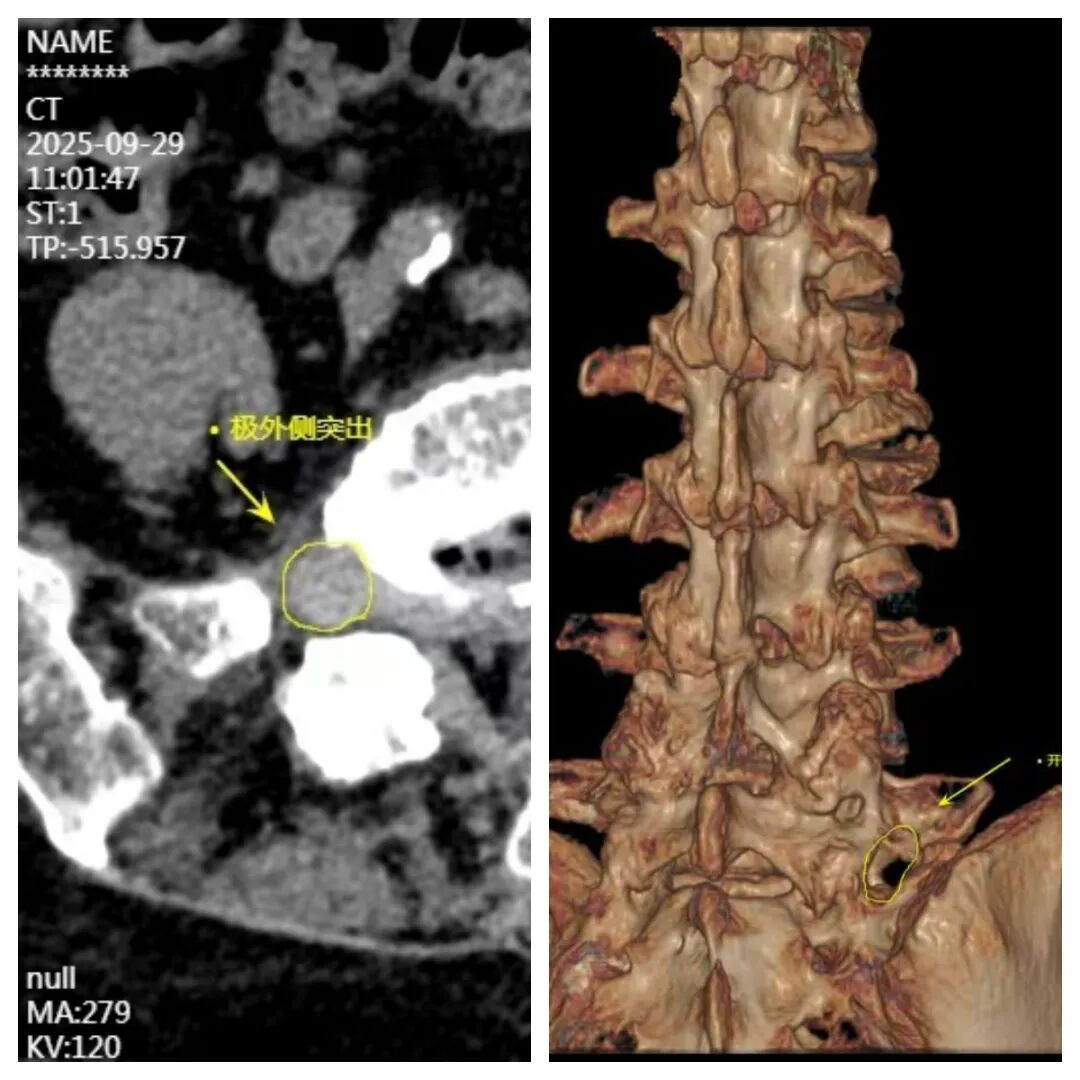

85岁的张女士被右腿疼痛折磨多年,辗转多家医院,尝试多种方法,始终未能好转。经过淄博市第一医院脊柱外科陈越林主任医师诊断为少见的“极外侧型腰椎间盘突出症”。该类型突出位置特殊,且患者高龄,合并有高血压、冠心病、泌尿道感染等多种基础疾病,麻醉与手术风险极高。为确保患者安全,由张店院区骨病中心牵头在术前组织了多学科协作诊疗,神经内科主任张涛、心血管内二科主任赵永刚、手术麻醉科副主任朱修源、泌尿外科医师毕文浩进行联合会诊,共同制定了麻醉预案及围手术期管理策略。在手术室丁秀洁护士长、程翔麻醉医师、孙宁泽护士及病房值班医护配合下,陈越林手术团队使用UBE技术为张女士顺利摘除突出的极外侧椎间盘。手术过程顺利,出血极少。术后,张女士先前难以忍受的右下肢放射痛症状即刻得到有效缓解。